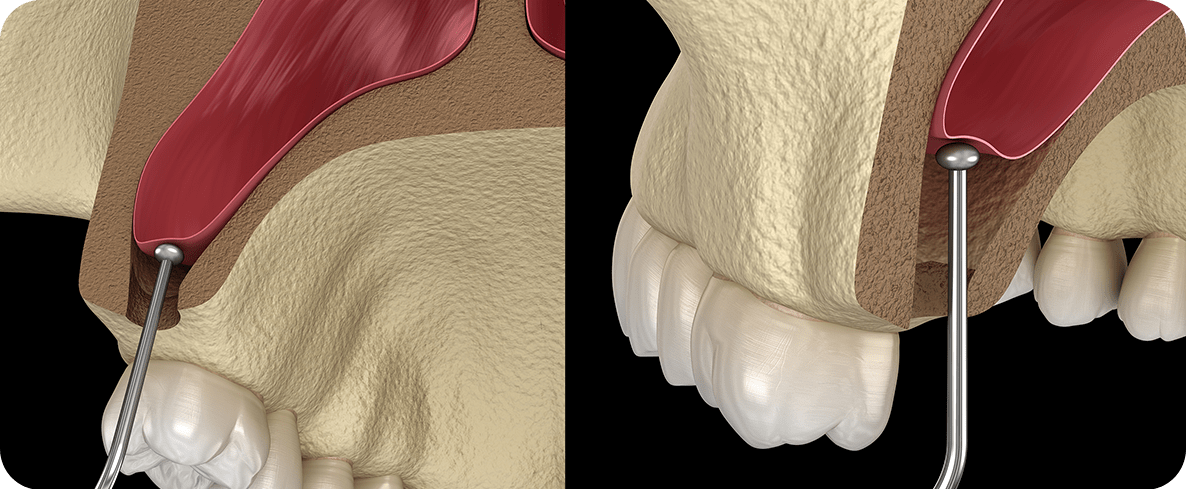

상악동거상술

상악에 임플란트를 식립할 만한 잇몸뼈가

충분치 않은 경우 상악동의 하방 벽을 들어 올려

공간을 확보하는 시술으로

해당 부위에 뼈이식을 실시해 골 형성을 유도하고

회복해 안정적인 임플란트 식립을 가능케 합니다.

상악에 임플란트를 식립할만한 잇몸뼈가 충분치 않은 경우

상악동의 하방벽을 들어올려 공간을 확보하는 시술으로

해당부위에 뼈이식을 실시해 골형성을 유도하고 회복해

안정적인 임플란트 식립을 가능케 합니다.

상악동 거상술은 상악동의 아주 얇은 하방 벽을 들어 올려야 하기에 섬세한 작업이 필요합니다.

치료 과정에서의 실수가 다른 기관에 염증을 일으킬 수 있고

임플란트의 탈락과도 밀접한 연관이 있기 때문에

진단 과정에서부터 상악동의 크기나 형태, 상악동 염증의 유무,

치조골의 두께 등을 정확하게 파악해야 하며, 의사의 숙련도가 뒷받침되어야 합니다.